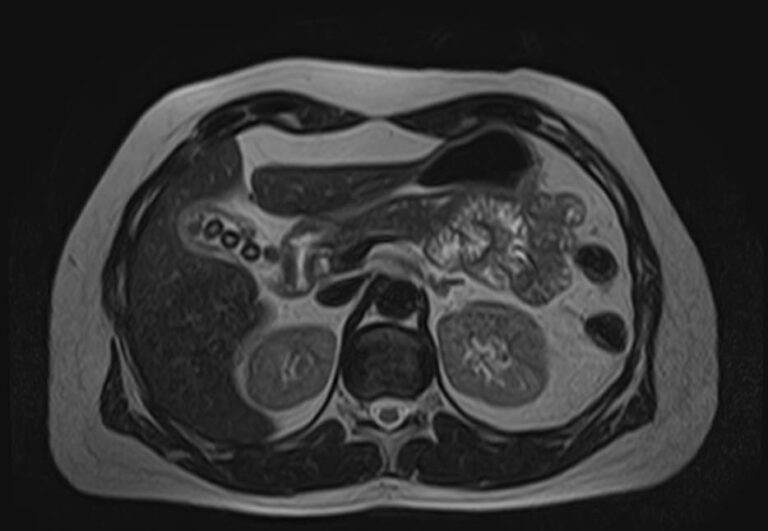

Современным методом обследования для диагностики заболеваний поджелудочной железы является магнитно-резонансная томография. В клинике «Доступная медицина» МРТ поджелудочной железы проводится на новейшем высокопольном томографе экспертного уровня TOSHIBA VANTAGE TITAN 1,5 Тесла, который позволяет получать послойные изображения исследуемой зоны с высокой степенью разрешения. Для лучшей визуализации и выявления минимальных изменений в органе применяется контрастное усиление путем внутривенного введения гадолиниевого контрастного препарата (Магневист, Гадовист, Омнискан и др).

С помощью компьютерного моделирования аппарат создает объемные изображения превосходного качества. Возможности аппарата позволяют поставить точный и достоверный диагноз, что дает возможность выявлять заболевания на ранних стадиях и назначать своевременное лечение.

В процессе МРТ поджелудочной железы получают серию снимков органа, по которым можно оценить следующие параметры:

МР-томография выступает уточняющим методом диагностики при сомнительных результатах УЗИ. Процедура позволяет определить характер, локализацию и масштабы патологического процесса.

Метод применяют при подозрении на онкологический процесс для первичной дифференциации доброкачественных и злокачественных опухолей. Подробные сведения об анатомии поджелудочной железы позволяют исключить осложнения панкреатита. МРТ также применяется для подготовки к хирургическим операциям и контроля результативности лечения.